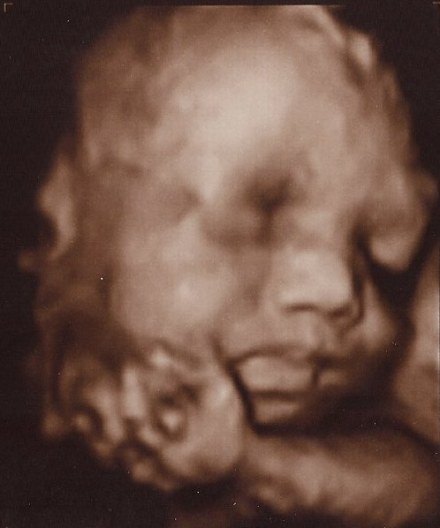

Vi glæder os sådan til at møde hende. Hende med fars næse og mund, hende som de siger har masser af hår på hovedet. Vores lækre lille halvkoreanske skønhed! Vores prinsesse, solskin og lille mirakel

Fra streger, til første mave, til NF til 3D til stor mave!